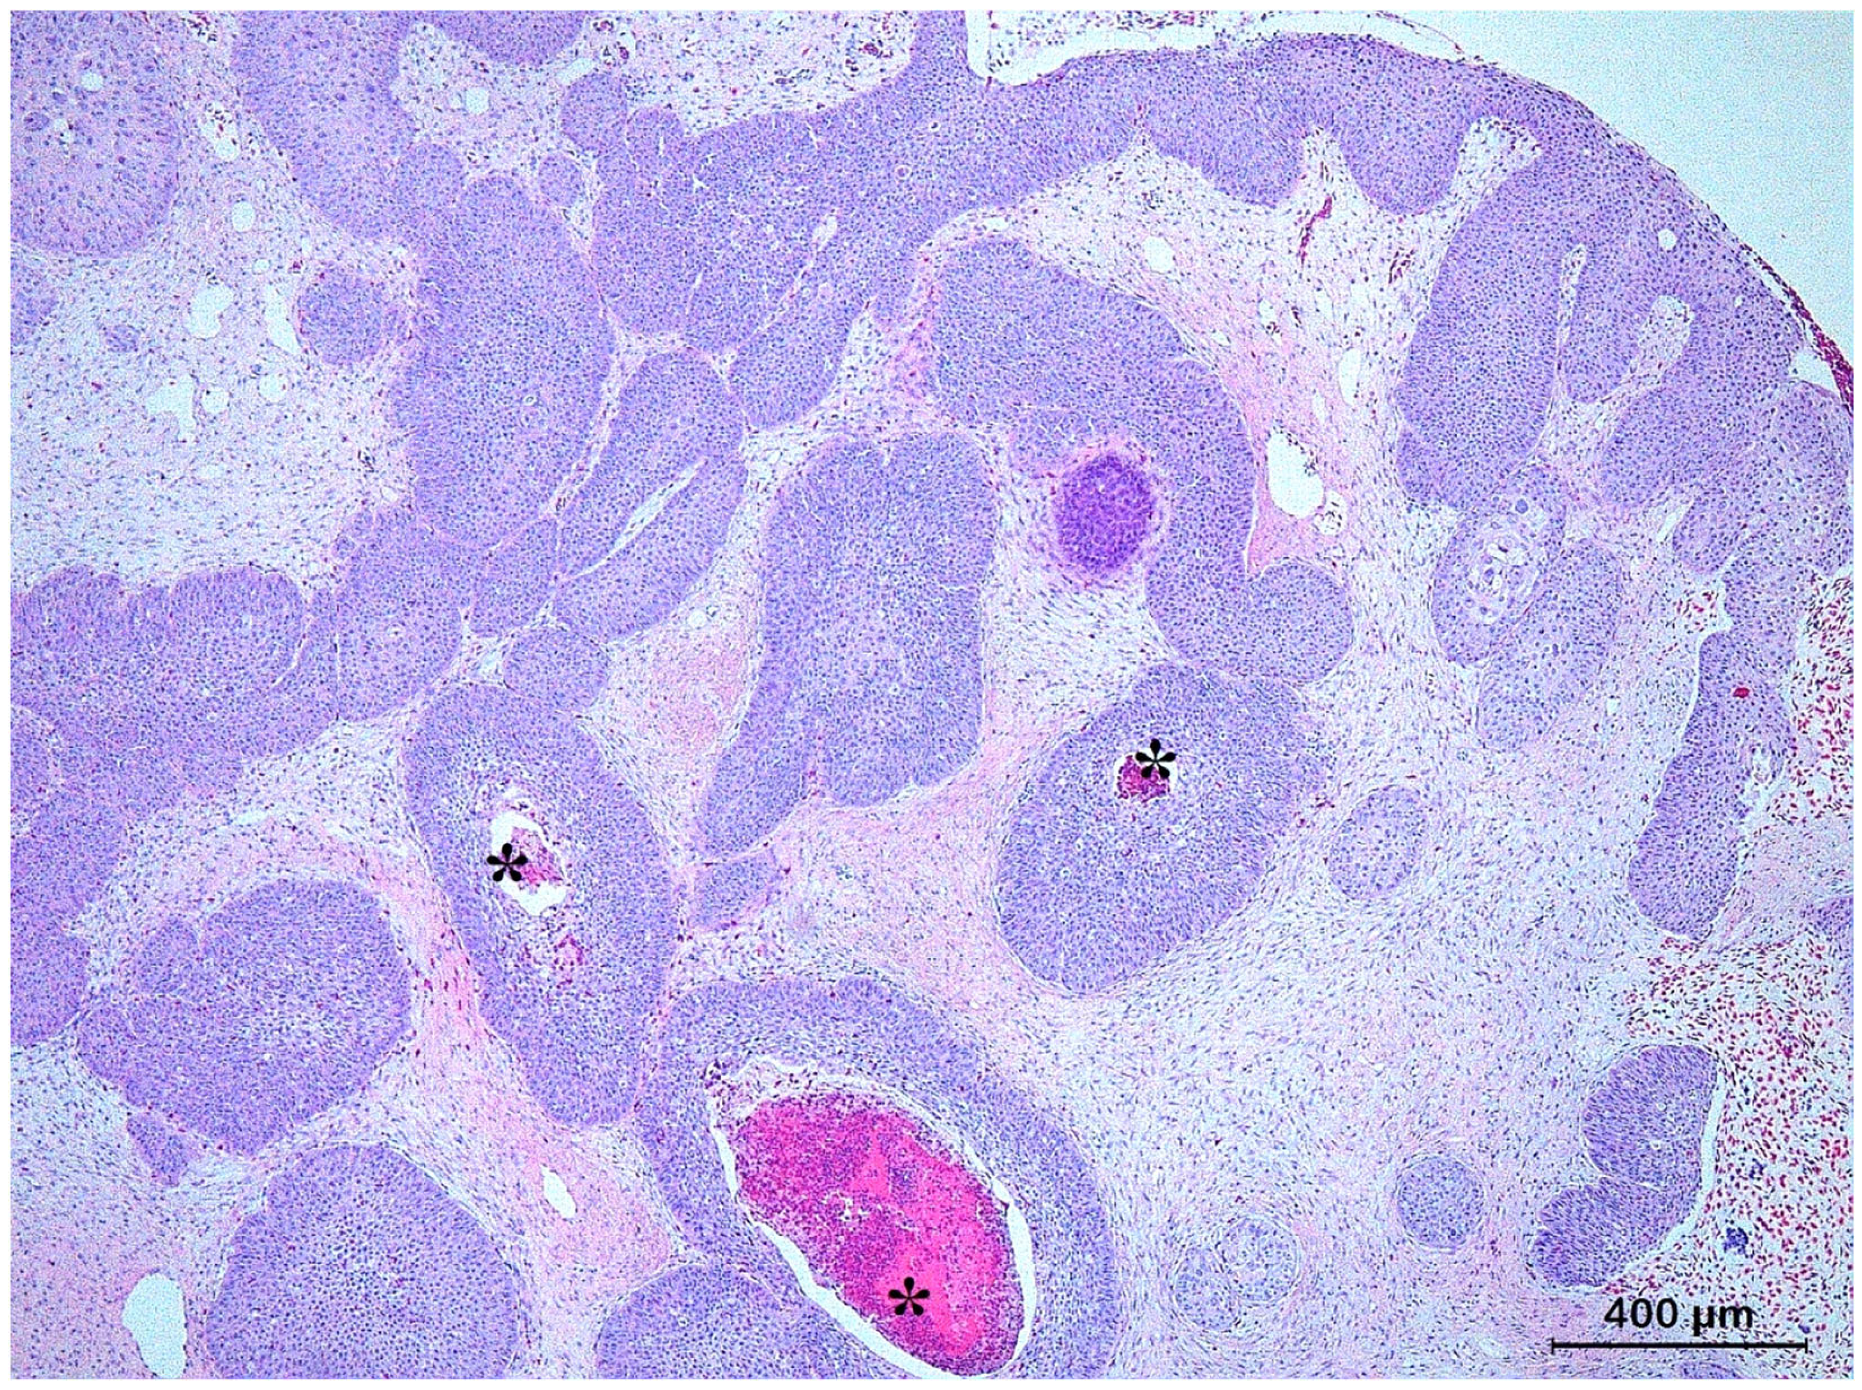

3.3. Basal Cell Carcinoma and Its Histological Variants